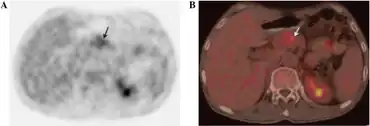

| a,b)Glucagonoma syndrome- the presence of a lesion with mild 18F-fludeoxyglucose uptake, which corresponds to location of tumour | |